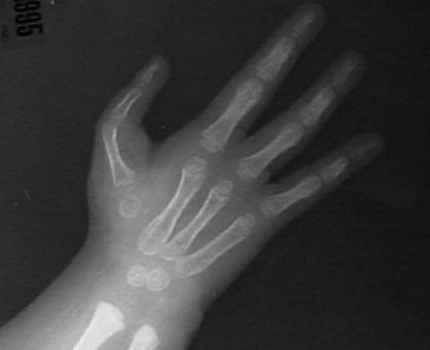

Radiographs

HL6